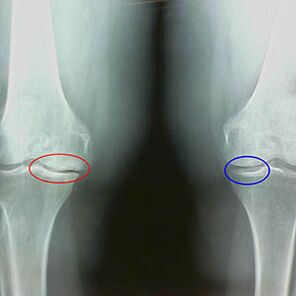

Stanovení stupně artrózy se vyskytuje pomocí x -vyzařováníOdhalení účasti na patologickém procesu kostních struktur. Jejich změna naznačuje, že svalový systém byl v nerovnováze po dobu 5-10 let. Zpravidla, lidé Několik let zažívají bolestivé bolesti.

V první fázi artrózy, která je detekována náhodou, dochází k mírnému zvýšení kostních ostruček. Výrůstky se objevují v místech největší nestability kloubu. Pacienti obvykle zažívají během pohybu zřídka bolest nebo nepohodlí.

Druhá fáze artrózy je považována za snadnou. Rentgenový snímek odhaluje významné ostruhy kostí, ale chrupavka není ovlivněna. Množství synoviální tekutiny je sníženo, ale příznaky bolesti se objevují po dlouhém chůzi a běhu, tuhost v kloubu a bolestivosti při ohýbání a v poloze na kolenou.

Brzy x -ray rysy druhé fáze artrózy kolena:

- špičaté okraje inter -odplatků na holenní kosti, kde je připojen křížový vazu;

- zúžení kloubní mezery na střední straně;

- Špičkové okraje kondylů kostí na středních stranách, méně často v laterálu - v závislosti na vývoji deformace valgus nebo varior kloubů.

Pro druhou fázi v Larsenu Zúžení mezery kloubu o více než 50% je charakteristické, ale to lze zkontrolovat pouze v dynamice nebo porovnání s na rozdíl od kloubu.

Rentgenový snímek ukazuje přítomnost osteofytů, změnu prostoru mezi femorálními a holenními kosti, což ukazuje na ztrátu chrupavky v koleni. Někdy x -ray kolenních kloubů vykazuje významné známky opotřebení chrupavky, ale pacienti nezažívají významnou bolest.Naopak, artróza první fáze může narušit funkci kolena, protože příčinou bolesti jsou hypotonické svaly.